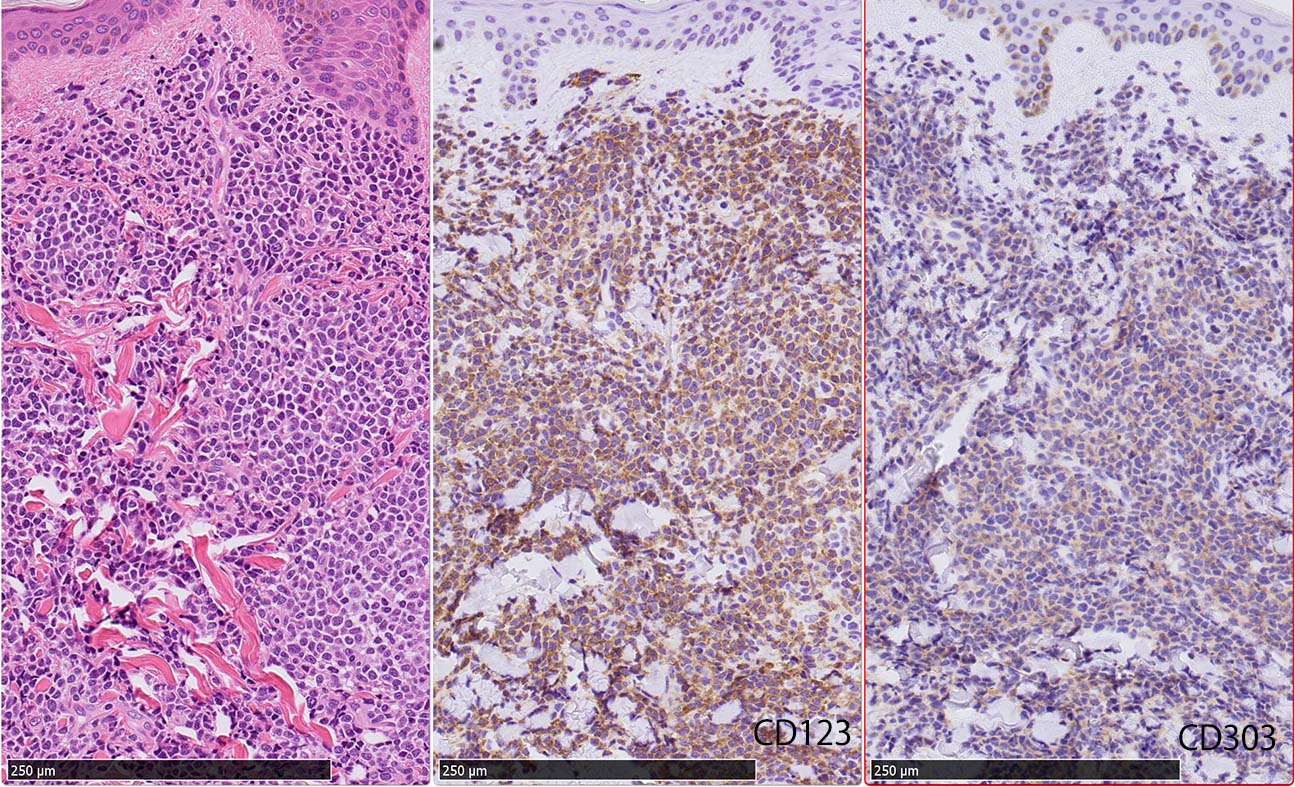

皮膚病変

blasticという名前から「大型細胞」を想起するが, この症例のようなclassical typeの細胞は思ったほど大きくはない. CD123陰性リンパ球とくらべてもあまり大きくないことがわかる.(散在する大型細胞はlysozyme+)

形態は均一で多型はめだたない.

免疫染色

IWT-case: 4つの点で囲んだ紅斑から生検.

皮膚病変は64-100%の症例で認められ皮膚病変が契機となり診断されることも多い.

マクロ所見は多彩で, 孤在性から播種性の分布を呈し, 腫瘤, 局面, 紅斑いずれの形態もとりえる.

腫瘍細胞は真皮を主座として, 皮下脂肪織まで, びまん性かつ単調monotonousに増殖することが多く, 表皮向性はみられない. 本例では血管や付属器中心あるいは脂肪織内に結節状の浸潤増殖を示した.

本例皮膚真皮増殖細胞はCD4+, CD56+, CD123+, CD303+, lysozyme(-). がん研有明病院, Sakamoto K, Takeuchi K先生にconsultationを行い, TCF4, TCL1の陽性が確認された.(consultationを受けていただいた両先生に深謝いたします.)